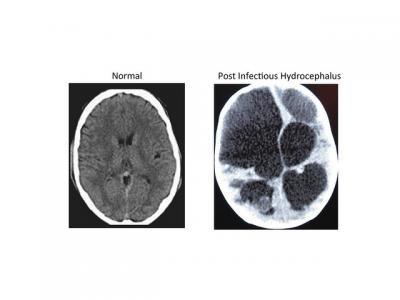

These images are normal (left) and postinfectious (right) hydrocephalus CT scans.

(Photo Credit: Steven Schiff, Penn State)